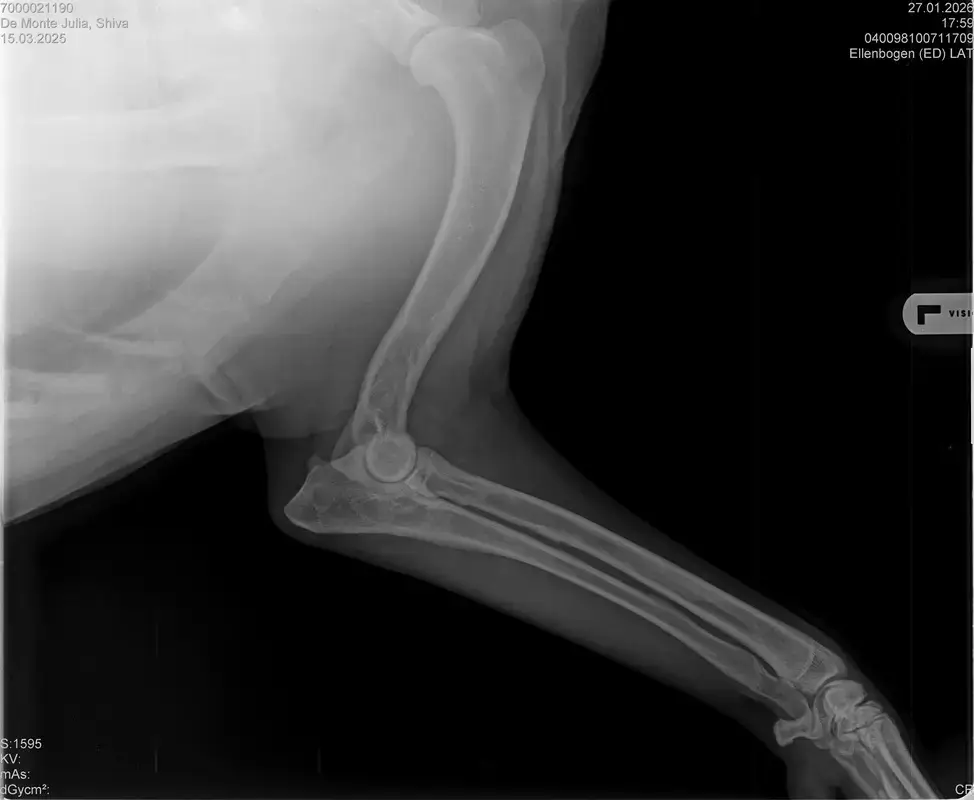

Vorige Woche kam mir Shiva verändert vor, nicht der aufgeweckte Spaßvogel der er sonst ist. Ich dacht vl ist er im Garten iwie blöd ausgerutscht weil unser gesamtes Grundstück über Wochen von einer dicken Eisschicht überzogen war. Er lag viel rum, zuviel da er doch zu den Wirbelwinden unter den Junghunden gehört. Er quetschte sich zum schlafen an mich ran, was auch untypisch für ihn ist. Er ist immer so „iiiii fass mich nicht an“. Ich nehms ihn nicht böse er ist nicht der große Kuschler :D Hat er wohl von mir :D :D aber er pickte nur an mir dran, ruhen ohne Körperkontakt war nicht möglich. Fand ich schön aber da ich wusste dass es nicht Shiva ist machte ich mir schon Sorgen… Am nächsten Tag wollte ich ihn bürsten alles war wie immer, er legte sich hin und sah mir zu wie ich einen Fellberg stapelte. Bei seinen Hinterpfoten hörte ich auf und dachte mir ich fühl mal vorsichtig.. Plötzlich knurrte er mich an vor Schreck weil ich damit überhaupt nicht gerechnet hatte zuckte ich reflexartig zurück (was lt Trainerin ein Fehler war)… Aber ich hab nicht mit einer derartigen Reaktion gerechnet, Shiva hatte schon 2 kleine Verletzungen die ich ohne Probleme verarzten konnte. Am nächsten Tag gings ab zum TA. Mit Maulkorb da ich nichts riskieren wollte. Nach der Untersuchung wo er auch mehrmals knurrte gings ab zum röntgen. Und das riss mir den Boden unter den Füßen weg. Dann die Aussage von der TA „ich weiß sie wollen einen gesunden jungen Hund aber das ist Shiva leider nicht“. Was jetzt? Er ist so ein aufgewecktes Kerlchen, absolute Lieblingsbeschäftigung ist Parcour. Er macht es so gern, ja auch UO und Suchspiele aber das leuchten in seinen Augen wenn wir Geräte machen :( (er macht noch keine schweren Geräte wie A Tafeln oder springen… Aber die seichten macht er mit absoluter Leidenschaft.. Ruhe halten über mehrere Monate… nur langsames gehen oder schnüffeln.. puh ich weiß nicht wie ich ihm verbieten soll zu rennen und zu toben… Vl habt ihr Tipps für mich. Im Anhang der Befund und ein paar Bilder vom kleinen Wirbelwind. <3

• Naja die Diagnose kommt von einem „Facharzt“, lt TA war ihrerseits alles i.O. Sie wollte noch sicher gehen und die Bilder zur weiteren Befundung einschicken und das kam dabei raus. Und der Therapievorschlag beläuft sich auf Ruhe, Ruhe und noch mehr Ruhe. Und einer Schmertherapie von Gabapentin 800mg 1/2 Tablette 2x tgl, Carprodyl 120mg 1 1/2 Tabletten 1x tgl und TamaCan CBD Tropfen 10-15 Tropfen 2x tgl. 1x in der Woche soll ich telefonisch Auskunft geben wie es Shiva geht. Das ganze mal für 14 Tage. Sie meinte noch sie hat viele Junghunde die ein Leben lang Schmerzmittel nehmem müssten. Die Röhrenknochenentzündung heilt in der Regel von selber der Rest gehört beobachtet… Ich weiß im Moment auch nocht so recht.. Er tut mir nur wahnsinnig leid mit sovielen Diagnosen und für mich war erstmal vorrangig ihn schmerzfrei zu bekommen. Das ist er inzwischen und versteht die Welt nicht mehr warum er nicht wie sonst spielen und arbeiten darf. Im Anhang noch Röntgenbilder falls sich jemand damit auskennt bzw Interesse hat..

• Ok, die Röntgenbilder sind aber auch extrem schlecht.

Panostitis ist idR sehr schmerzhaft, aber nicht unüblich und heilt in der Regel von alleine aus, wichtig dabei ist schonen und Entzündungshemmer zu geben, damit das nicht chronisch wird. Ich denke, dass die Akut bemerkbaren Schmerzen hauptsächlich davon kommen. Also da passt die Empfehlung deiner TÄ für's Erste auf jeden Fall.

Wenn dieser Panostitis-schub rum ist, würde ich dem Rest nochmal nachgehen. Man kann bei Dr. Tellhelm ( SV Gutachter) ein privatgutachten in Auftrag geben, das kostet um die 100€. Da kriegst du halt ne konkrete Einstufung und nicht "verdacht auf" und "könnte hiermit ODER damit in Verbindung stehen", etc.

Ich denke aber, dass du für ein Gutachten von Tellhelm nochmal neu röntgen lassen musst, ich finde, dass das Bild der Hüfte (HD und LÜW wird da beurteilt) und die Draufsicht auf die Ellenbogen (nötig zur Beurteilung von ED) unterirdisch sind!